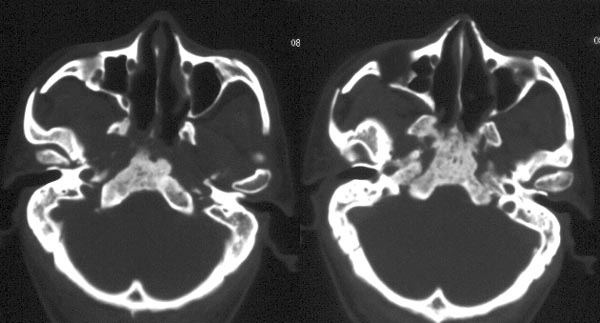

患者放疗后半年ct复查

ct平扫:鼻咽右侧壁增厚,右侧咽隐窝消失,右侧咽旁间隙变窄,但病灶较原片明显缩小。原片所见鼻咽顶壁、顶后壁、后壁增厚,现已基本恢复正常,原片见枕骨斜坡、蝶骨基底部骨质破坏,现亦已修复,为高密度骨质充填。颈深筋膜各间隙未见肿大淋巴结。

ct诊断:鼻咽癌放疗后,肿物较前片明显缩小,颅底骨质破坏基本修复。